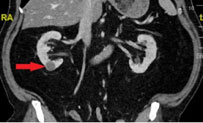

Ultraschallbild einer Nierenzyste Computertomografie einer Nierenzyste

Computertomografie einer Nierenzyste

Die Abklärung umfasst neben dem Ultraschall oft auch eine Bildgebung mit Computertomografie (CT) oder Magnetresonanztomografie (MRT).

Neben einer körperlichen Untersuchung, sowie Blut- und Urinprobe werden Nierenzysten zuerst mit dem Ultraschall untersucht und beurteilt. Manchmal muss zusätzlich eine Computertomografie oder Magnetresonanztomografie durchgeführt werden, um entscheiden zu können ob es sich wirklich um eine «harmlose» Nierenzyste handelt.